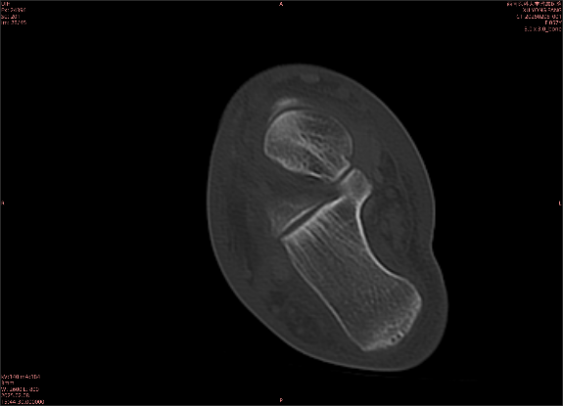

隱性骨折在MRI表現(xiàn)為T(mén)1WI序列上見(jiàn)由關(guān)節(jié)面向骨干走行的形態(tài)各異低信號(hào)區(qū),有線狀、條狀、紊亂低信號(hào),信號(hào)強(qiáng)度不均勻。與T1WI低信號(hào)改變相對(duì)應(yīng)部位在T2WI上表現(xiàn)為相應(yīng)形狀的高、低混雜信號(hào),且部分低信號(hào)周?chē)梢?jiàn)高信號(hào)水腫改變。STIR序列圖像上病灶呈顯著高信號(hào),與信號(hào)被抑制的臨近正常骨髓形成鮮明對(duì)比,分界也較T2WI成像更為清楚。脂肪組織抑制技術(shù)是MRI的一個(gè)重要性能,脂肪抑制技術(shù)在MRI應(yīng)用中可以改善組織對(duì)比和增加病變顯示機(jī)會(huì),這樣骨髓的脂肪抑制后就不會(huì)有任何信號(hào),而隱性骨折線及骨髓水腫的異常高信號(hào)就會(huì)更加明顯的顯示出來(lái)。

舉例圖像

專業(yè)解釋看不懂沒(méi)關(guān)系,大家看圖1和圖2就可以了,這是同一個(gè)患者跟骨的磁共振和CT圖像,圖1的紅色箭頭指示的黑線就是磁共振圖像顯示的骨折線,一目了然。而對(duì)比圖2的CT圖像上并未顯示異常。